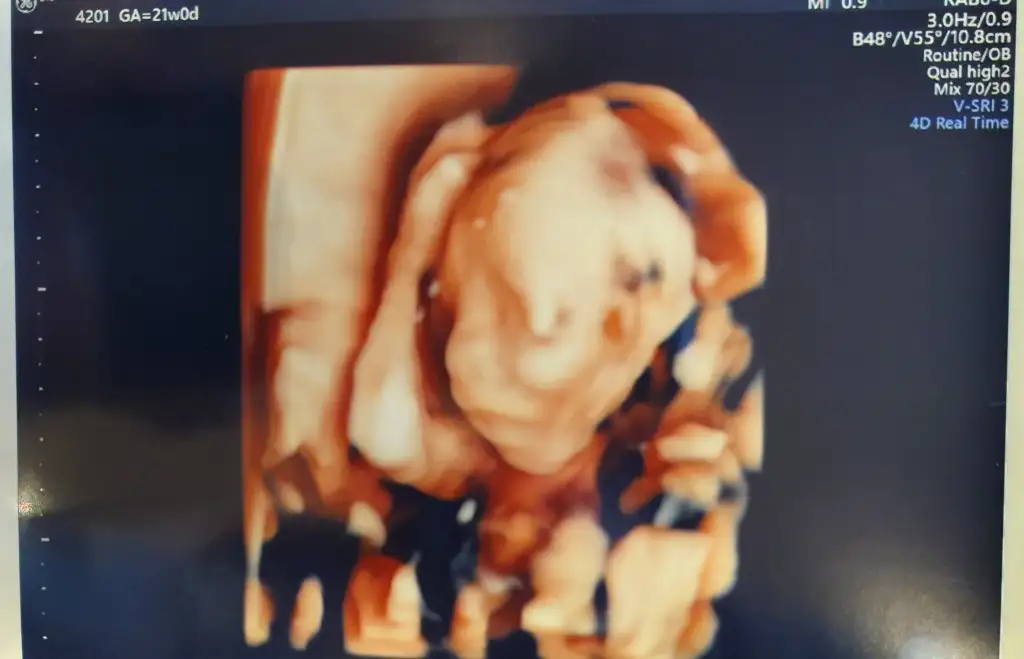

Bizim minnoşlar dertli hep elleri kafalarındakızlar selam. bugün detaylı ultrasonum vardı doktor bildiginiz hırpaladı beni 3-4 saat oldu hala kendime gelemedim. dün de şirket yemeği vardı 12 bucukta geldim eve belki onun da yorgunlugu var :/ çok şükür bebişimin tüm organları saglıklı herşeyi yolunda. plasenta da normal konuma gelmiş, çok rahatladım. muayenenin ortasında bizimki dönmedi bi türlü oyuzden bazı organlarına bakamadı, çıkın 10 dk hoplayın zıplayın çikolata yiyin öyle bir daha gelin dedigeldim sonra görebildi çok şükür ama muayene boyunca aleti okadar cok bastırdı ve karnımı okadar salladı ki sersem gibi oldum hala geçmedi. önceki detaylı ultrasonum hiç böyle değildi cok rahat gecmişti, bir de doktor klasik müzik filan açmıştı ortam daha rahatlatıcıydı, bu gittigim perinatalog beni geriyor biraz. çok şükür bu süreci de atlattım diyorum en azından, hepiniz icin saglıklı kontroller diliyorum